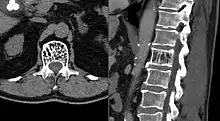

| Axial and sagittal CT views of a vertebral hemangioma | |

CT

On computed tomography (CT) or radiograph, VHs can cause rarefaction with vertical striations (often referred to as corduroy pattern) or a coarse honeycomb appearance. A polka-dot appearance on CT scan represents a cross-section of reinforced trabeculae.[11][13] CT best defines the bony architecture and is the best diagnostic imaging method.[14]